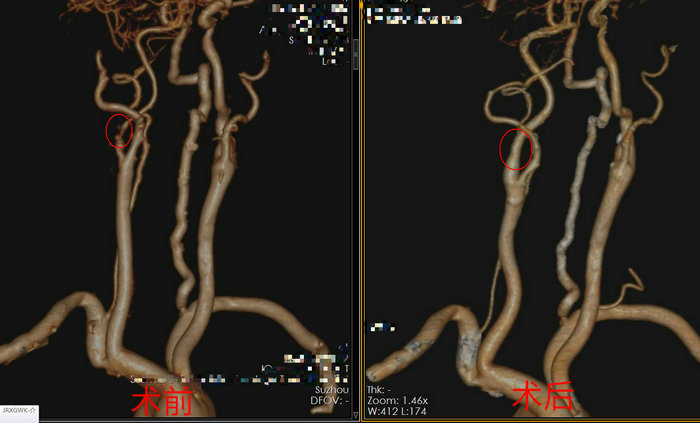

为了从根本上解决沈大爷的视力问题,徐林立即将其转诊至介入血管外科。经过专家的会诊和评估,沈大爷接受了颈动脉内膜剥脱和颈内动脉成形术。手术过程顺利,术后沈大爷的视物模糊症状得到了明显缓解。